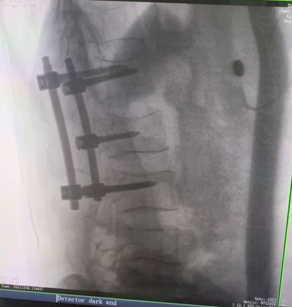

例如治療先天性脊柱側后凸畸形,由于脊柱自身復雜的解剖結構限制,使得脊柱外科手術對于精確度有著較高要求。以往我們只能采用傳統的正側位圖像來判斷螺釘置入的位置,現在三維C形臂特有的類CT斷層成像,使得治療過程可視化,立體化,在術中非常直觀地判斷螺釘植入的準確度。可有效引導術者植入后路螺釘并切除半錐體。同時可以在術中實時驗證手術效果。有效地縮短了手術時間,降低手術風險,避免了不必要的術后翻修手術。

另外,三維C形臂采用12英寸(30cm x 30cm)的平板探測器,成像區域大,有效成像面積比9英寸傳統影增提升了100%,可一次拍七節頸椎、五節腰椎、十二節胸椎、雙側骶髂關節、股骨頭及單側盆骨。